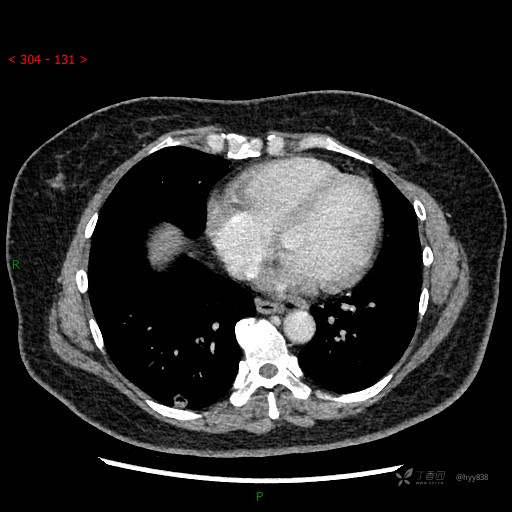

讨论:结节影像特点和性质?